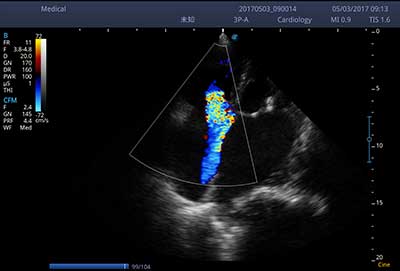

频谱自动包络

E3便携式彩色多普勒超声诊断系统拥有专业超声技术平台、高度集成化的硬件模块和结构设计、简便的操作流程、支持三探头接口全激活,兼顾了优质图像、轻便机身以及台便两用的临床使用需求。无论在常规超声科门诊检查,还是在急诊、麻醉、ICU、户外等各种应用场景。都能给您带来流程的操作体验。